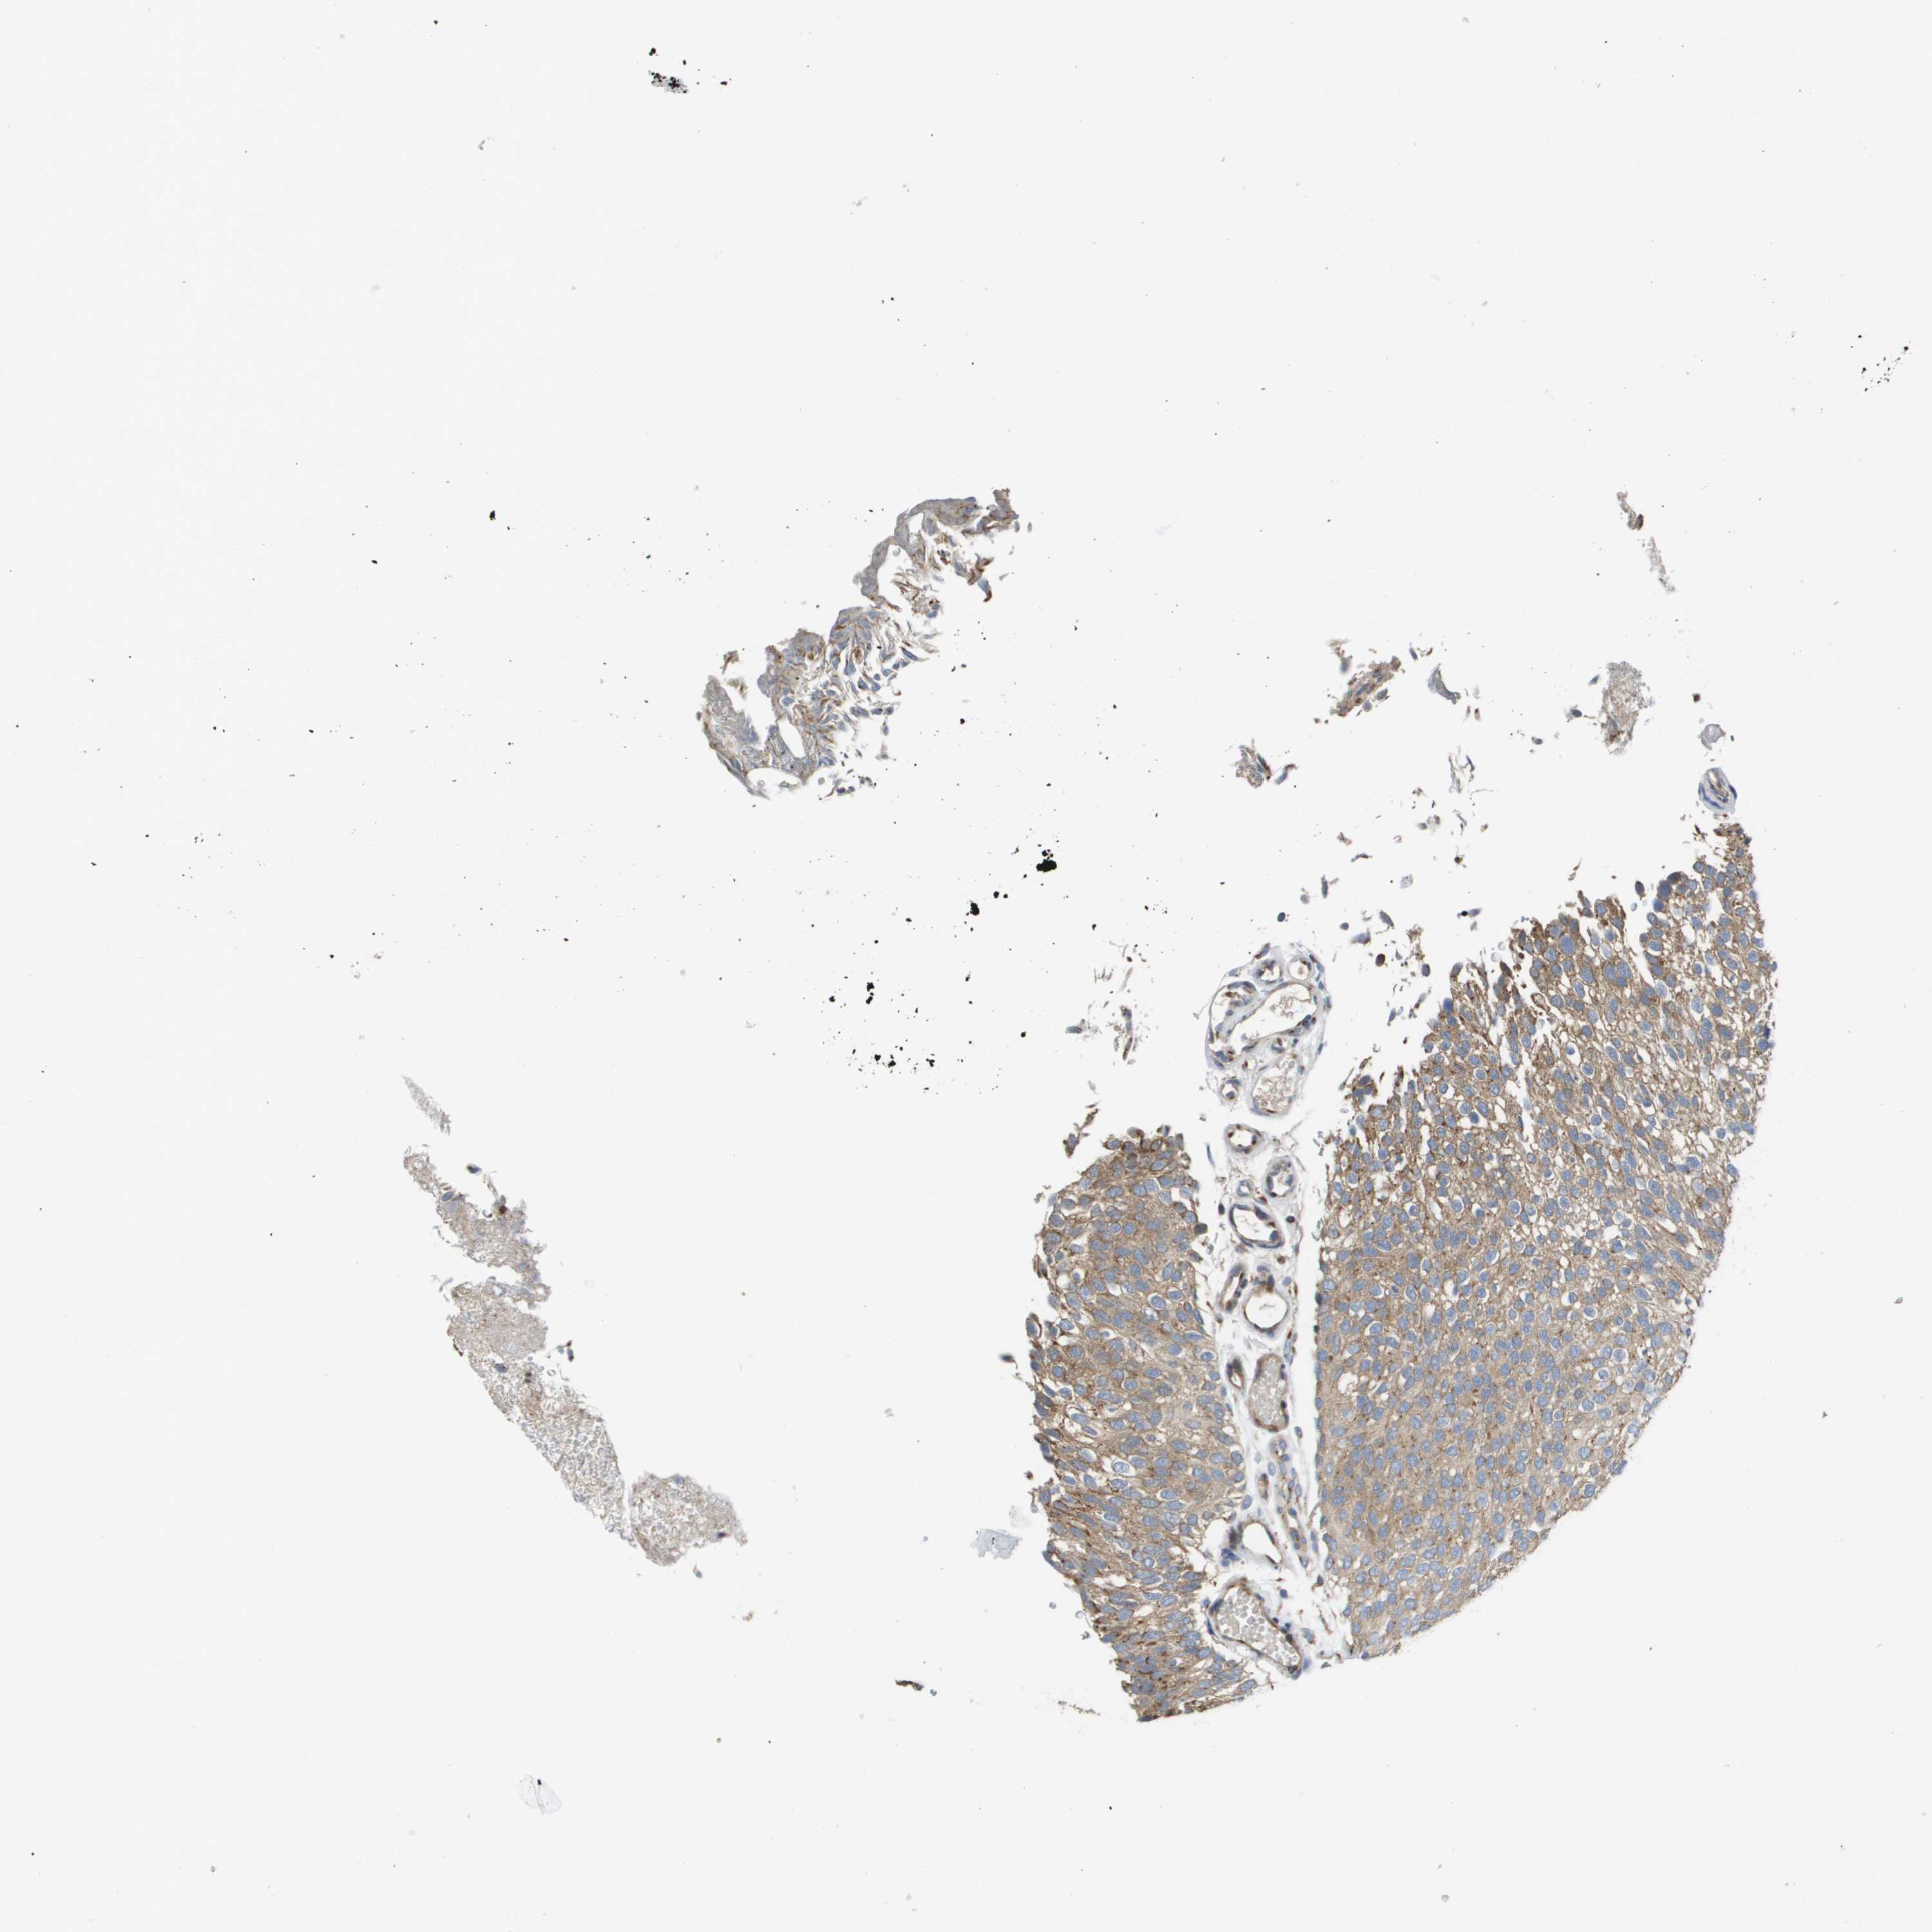

UROTHELIAL CANCER - Protein expressioni

A mouse-over function shows sample information and annotation data. Click on an image to view it in a full screen mode. Samples can be filtered based on level of antibody staining by selecting one or several of the following categories: high, medium, low and not detected. The assay and annotation is described here.

Note that samples used for immunohistochemistry by the Human Protein Atlas do not correspond to samples in the TCGA dataset.

Antibody stainingi

Antibody staining in the annotated cell types in the current human tissue is reported as not detected, low, medium, or high, based on conventional immunohistochemistry profiling in selected tissues. This score is based on the combination of the staining intensity and fraction of stained cells.

Each image is clickable and will lead to virtual microscopy that enables deeper exploration of all samples and also displays staining intensity scores, fraction scores and subcellular localization as well as patient and tissue information for each sample.

Antibody HPA006277

Antibody HPA006507

Antibody CAB017027

Staining

High

Medium

Low

Not detected

Intensity

Strong

Moderate

Weak

Negative

Quantity

>75%

75%-25%

<25%

None

Location

Nuclear

Cytoplasmic/membranous

Cytoplasmic/membranous,nuclear

Urothelial carcinoma, Low grade

Urothelial carcinoma, High grade